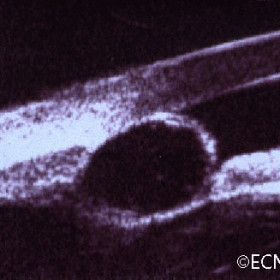

Iris Pigment Epithelial Cyst

Iris Pigment Epithelial Cyst - This unusual pupillary cyst (left) is demonstrated to be acoustically hollow on a transverse 20 MHz B-scan examination (right).